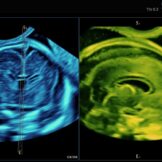

La caratteristica della tecnologia tridimensionale consiste nel fatto che non si lavora su un piano ma su un volume. Pertanto è possibile non solo, esaminare un determinato distretto nelle tre dimensioni, ma di manipolare sui tre piani il volume immagazzinato, consentendo di mettere in evidenza strutture anatomiche altrimenti difficilmente evidenziabili. Pertanto il 3D e il 4D non viene utilizzato esclusivamente per visualizzare il visino del feto* e le parti superficiali come le mani e i piedi ma per studiare il cervello (neurosonografia)**, l’apparato scheletrico *** e quello cardiocircolatorio****.